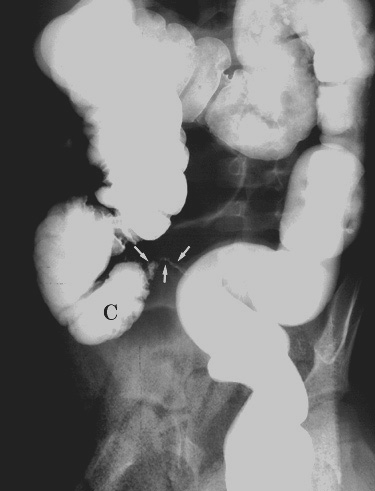

| Perforated appendicitis mimicking small bowel

obstruction. 4 year old girl presented with a four day history of anorexia, nausea, and vomiting. Physical examination was significant for pain on rectal examination. Plain films, a barium enema, and CT examination were obtained, shown below. |

|  | Figure 2. Right posterior oblique film obtained during single-contrast barium enema shows partial opacification of the appendix (arrows) which is irregular in contour. C = cecum. |